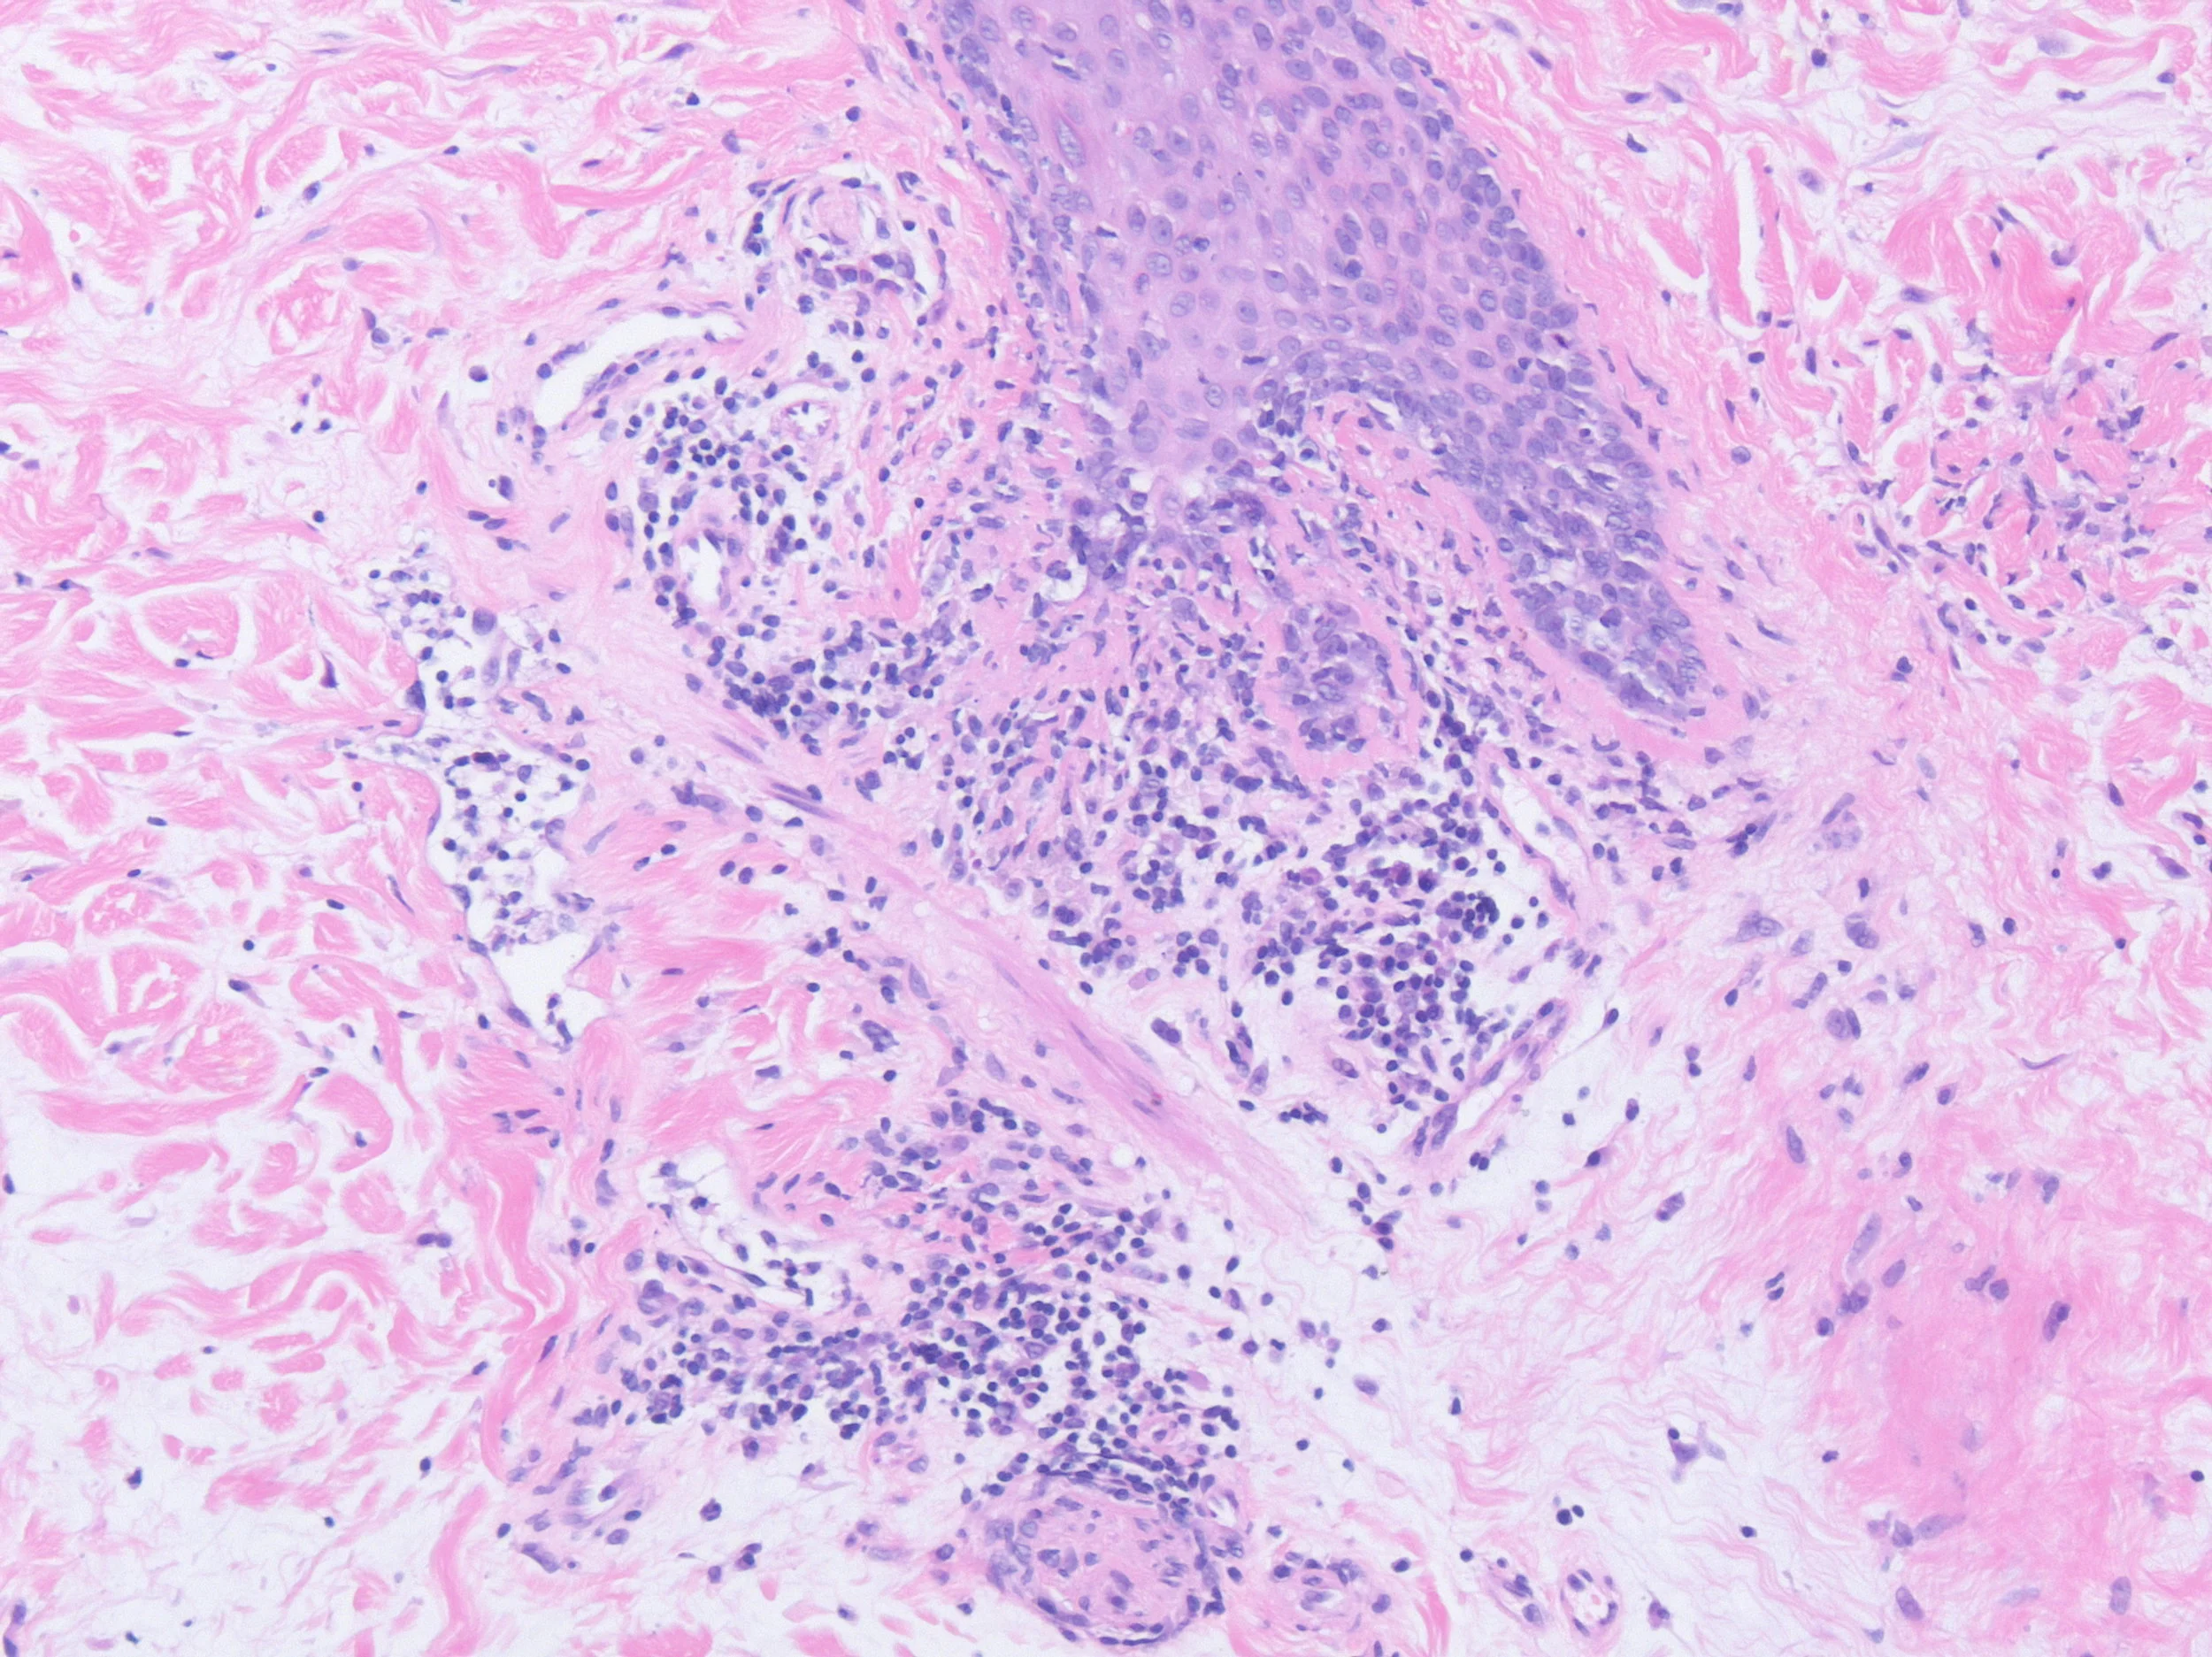

Left Shoulder Tip

Right Scalp